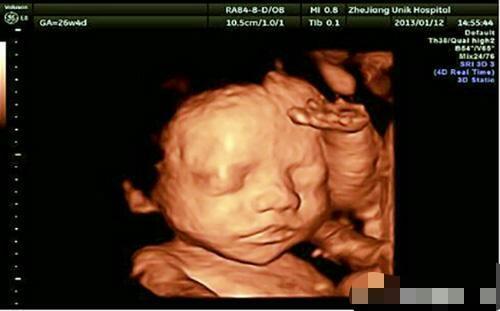

丽丽是那种对下一代很重视的孕妇,每一次产检她都不放过,力求胎儿健健康康的。怀孕二十周的时候丽丽找熟人做了B超。显示说是百分之八十是女胎,后来丽丽不甘心又多做了几次,均显示女胎。

令人崩溃的事情来了,刚做完引产手术,熟人告诉丽丽她怀孕时,其实是个男婴,胎儿有明显的小白点,但是小白点太小了,这在B超上很难发现。